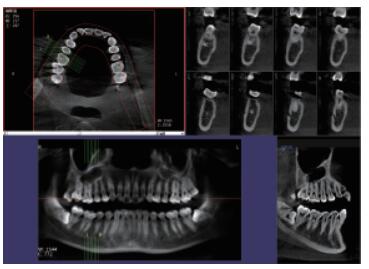

普愛(ài)口腔CT設(shè)備圖像質(zhì)量高產(chǎn)品說(shuō)明:

運(yùn)用口腔CT進(jìn)行檢查可以大大提高口腔科臨床水平。以普愛(ài)醫(yī)療口腔CT為例,(它)可用于口腔種植、正畸、牙體牙髓、牙周、顳下頜關(guān)節(jié)、頜面外科及其他診斷需求,它有掃描速度快、成像速度快、操作軟件專業(yè)性強(qiáng)等優(yōu)點(diǎn),它可以輔助各種臨床診斷與治療??谇籆T產(chǎn)品特點(diǎn):

CMOS成像質(zhì)量?jī)?yōu)

采用高端平板探測(cè)器,分辨率高、圖像質(zhì)量?jī)?yōu)。

三維重建任意斷層

專有三維重建算法,可提供任意位置高清斷層影像。

高清口腔全景影像

通過(guò)三維容積影像,提取高清口腔全景影像。

專有圖像處理軟件

專有圖像校正技術(shù),去除金屬偽影,提高圖像分辨率。

多平面組合重建

可同時(shí)觀察軸向面、冠狀面和矢狀面圖像,方便臨床診斷。